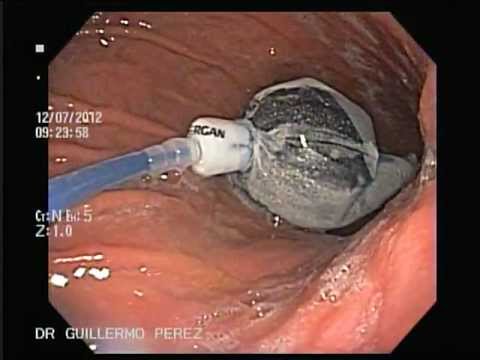

La técnica del balón intragástrico consiste en una esfera de látex llena de suero fisiológico colocado vía endoscópica en el estómago bajo sedación en un ingreso ambulatorio. Su principal efecto es la disminución de la motilidad del estómago reduciendo el tiempo de vaciado tras la ingesta de alimentos y provocando, en la mayoría de los casos, una sensación de saciedad temprana y demorada durante las comidas.